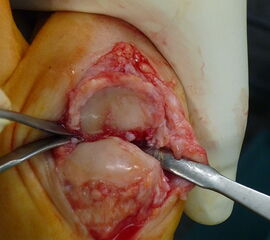

Die Implantation eines Swanson-Spacers in das Großzehengrundgelenk umfasst eine Resektion beider Gelenkflächen unter Erhalt der Sehnenstrukturen bei fortgeschrittener Arthrose am Großzehengrundgelenk. Das Verfahren ist nicht zur Achskorrektur bei Hallux valgus geeignet. Das Verfahren findet vor allem bei rheumatoider Arthritis Anwendung, kann aber auch bei Sekundärarthrose nach Keller-Brandes Operationen eingesetzt werden, soweit noch ausreichend Knochensubstanz vorhanden ist.

Die Knochenränder sollten abgerundet werden und bei scharfkantigem Knochen die Grommets als Spacerschutz verwendet werden. Die Osteotomie kann zur Optimierung der Beweglichkeit leicht schräg nach dorsal angelegt werden. Die Verwendung der Raspeln mit proximaler und distaler Unterscheidung (Bezeichnung P oder D) reduziert das Risiko der Perforation in das Interphalangeal-Gelenk, da die entsprechenden distalen Raspeln kürzer sind.